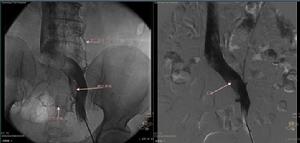

實驗室檢查和影像學檢查無特徵性,故對可疑病例, 應仔細詢問和分析病史,進行必要的輔助檢查,最有決定意義的是腹腔鏡直視下做肝組織活檢,不僅可靠, 而且安全(可對取材部位觀察出血情況,同時施以有效的止血) 但由於對本病的認識尚不夠深入、廣泛,加之患者和醫生懼怕出血等併發症,能夠實施此項檢查很少。肝靜脈和下腔靜脈造影對本病的診斷價值有限,但可用於與布-加氏綜合徵的鑑別。

最易與HOVD混淆的是布-加氏綜合徵(B-CS),以下幾點有助於鑑別:①兩者病因不同:B-CS最常見的原因是血液凝固性增高,如外傷、脫水、婦女衛生期、感染、腹部腫瘤和重勞後等;而HOVD與服用草藥 灌木茶和草茶等含野百合鹼的植物、接受放療、化療或免疫抑制藥有關。②B-CS的急性期雖也可有腹脹、肝區疼痛等症狀,但很少有發熱、嘔吐和腹瀉等伴隨症狀。急性期半數以上伴有下腔靜脈高壓綜合徵,如胸腹壁靜脈怒張、下肢水腫、會陰部及下肢淺靜脈曲張、足踝部潰瘍形成等,而HOVD則無。③下腔靜脈、肝靜脈造影可明確B-CS時主肝靜脈和下腔靜脈的阻塞部位、程度、範圍和側支循環形成情況等,HOVD則無陽性發現 ④B超可發現B-CS時下腔靜脈有無狹窄, 閉塞、阻塞程度, 有無血栓形成以及肝內側支形成,而HOVD多僅顯示肝大,急性期透聲性增強, 慢性期回聲增強, 增粗, 光點分布不均, 網狀回聲增強,與B-CS幾無區別。⑤肝活檢對B-CS和HOVD最有鑑別意義,B-CS時肝靜脈內可有血栓形成,且多在主肝靜脈出口部受累,HOVD則無肝靜脈血栓形成, 病變主要累及中央靜脈和小葉下靜脈,且為水腫性狹窄或纖維性狹窄。急性HOVD還應與急性肝炎和急性重型肝炎相鑑別。